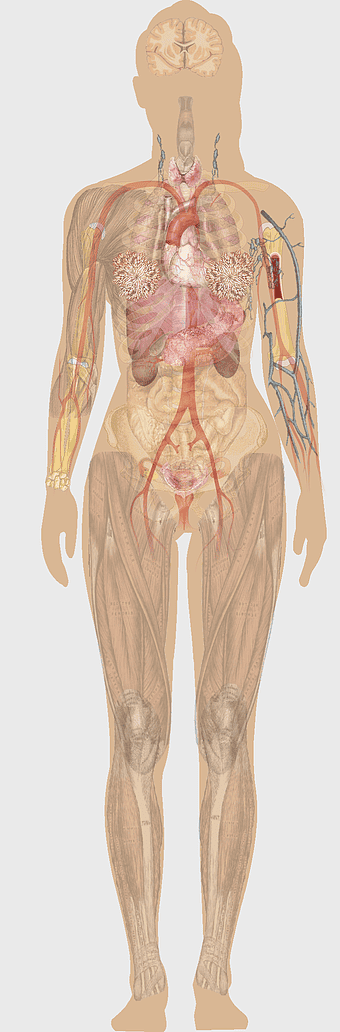

female anatomy diagram, human organ system chart, woman's body structure, female internal organs, human anatomy illustration, medical educational image, anatomical reference guide -

human anatomy diagram, digestive system illustration, human internal organs, Homo sapiens muscular system, anatomical art for education, systemic physiology chart, medical biology graphics -